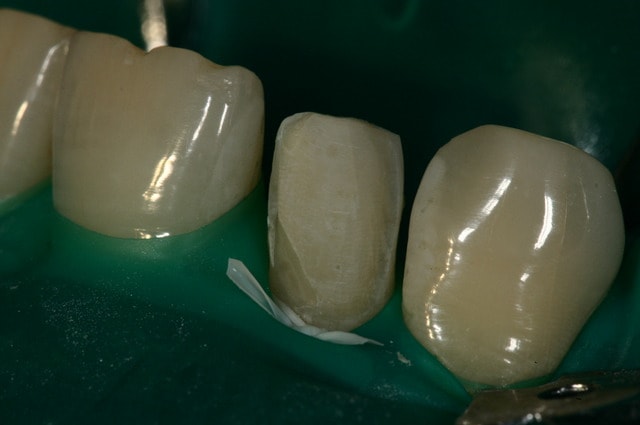

Il faut toujours essayer : parfois on est un peu sous gingival , ça à l'air mal barré et puis on met la digue et hop : magie !!! cf photo ci-joint.

Digue si6cja - Eugenol